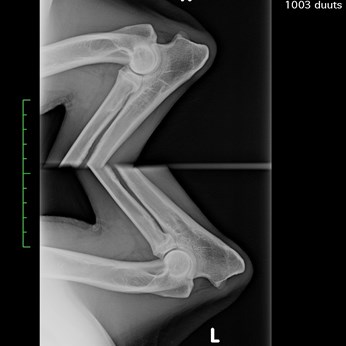

Name: Andrea von Haus Ka und Mi (Duuts)

Gender: Female

Date of birth: 28-06-2017